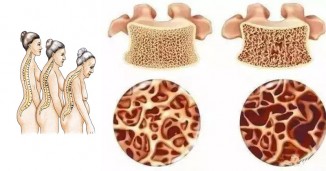

არაჩვეულებრივი ხალხური რეცეპტები ოსტეოპოროზის სამკურნალოდ!

ოსტეოპოროზი - დაავადება დაკავშირებულია ძვლების სიმყარესა და სიმკვრივესთან, მათი მოტეხილობების მაღალ რისკთან. ასეტი მოტეხილობები ემართებათ უმნიშვნელო..